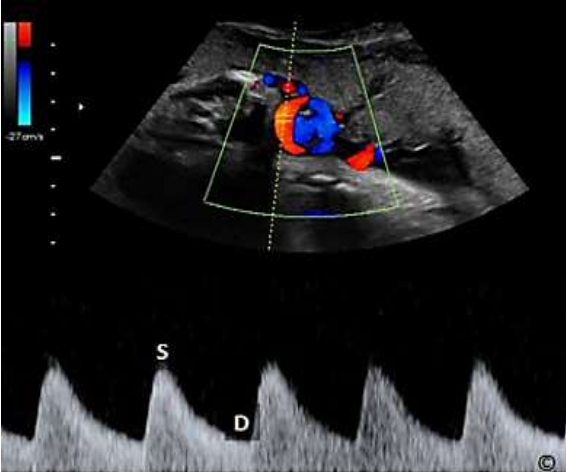

Assinale a alternativa que apresenta qual a estrutura representada na imagem a seguir.